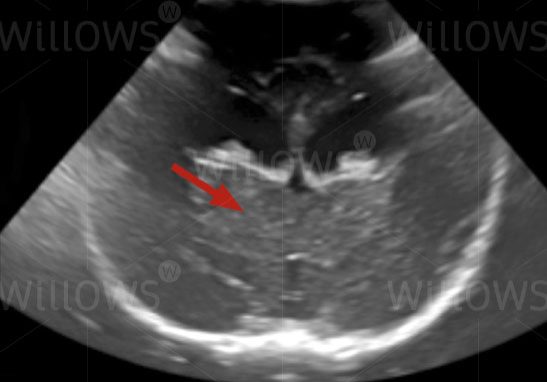

Ultrasound scan of the brain (arrow) through the soft spot on a skull in an infant– the detail seen is very limited compared to the MRI scan. This view is a cross-section seen from the back